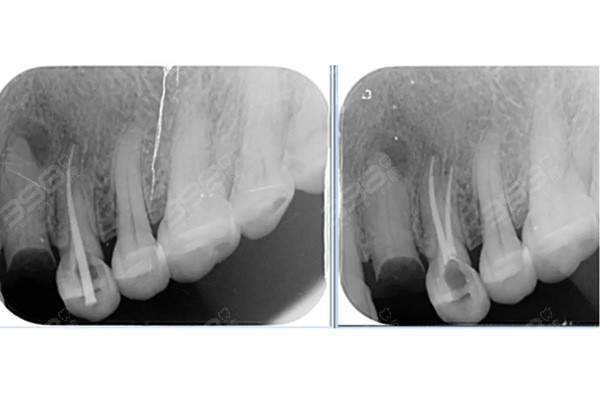

根管治療是一種通過清除牙齒內部感染物質,對牙齒進行修復和恢復的方法,這種方法適用于牙髓炎、根尖周炎等牙齒疾病的治療,根管治療的主要目的是消除感染、防止再次感染,并恢復牙齒的正常功能。

2、治療費用:根管治療過程中,醫生需要進行清創、消毒、填充等操作,這些操作產生的費用是根管治療總費用的主要部分。